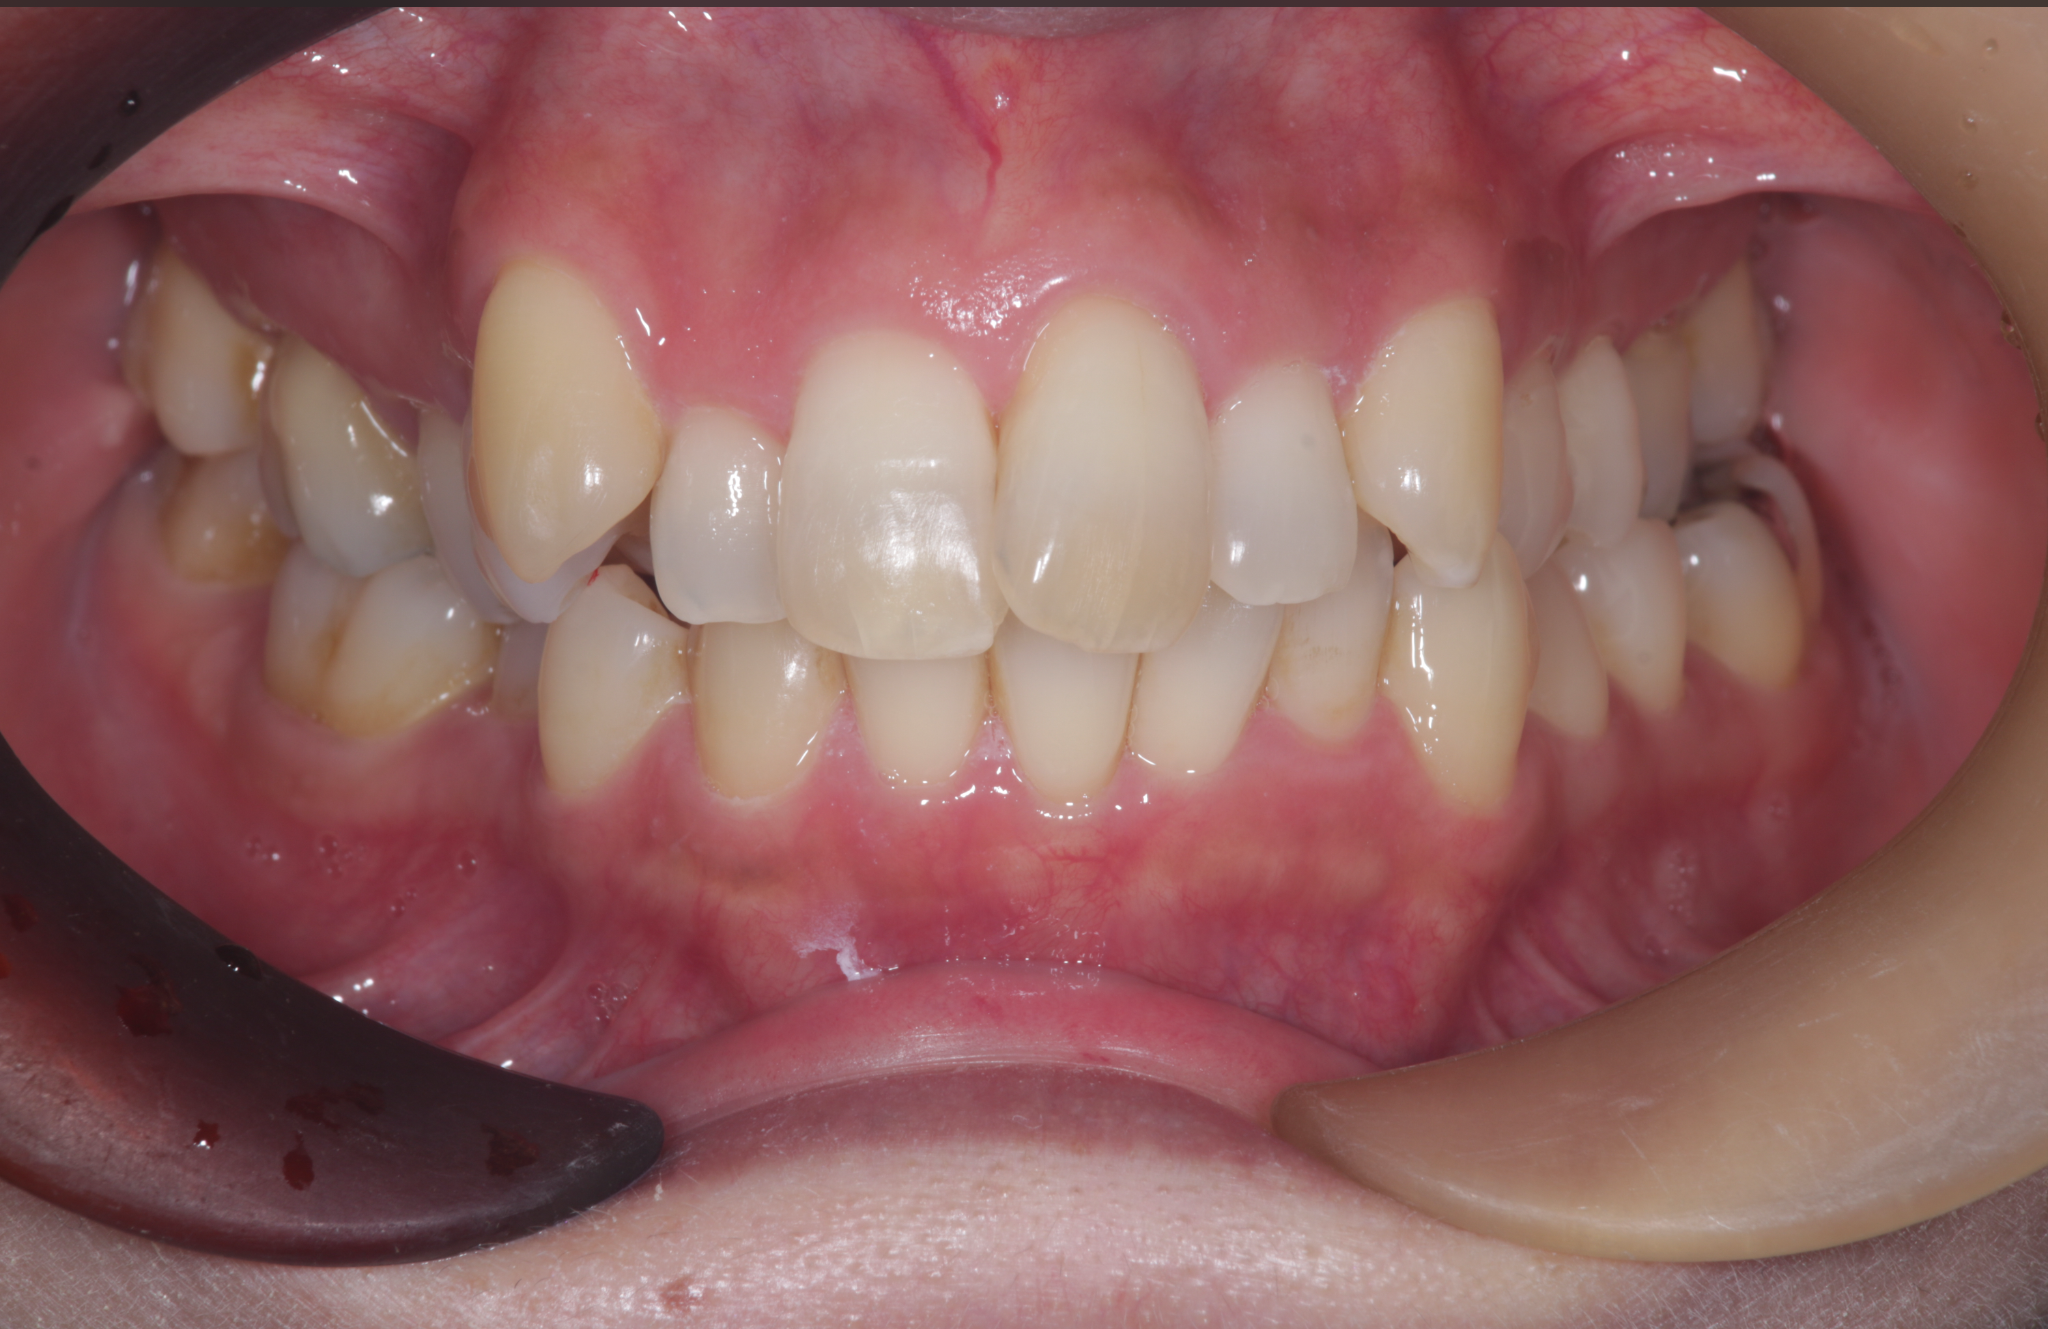

術後の状態

治療概要

| 患者さんの状態 | 叢生 |

|---|---|

| 治療内容 | MEAWを用いた矯正治療(非抜歯) |

| 治療期間 | 約2年 |

| 治療費用 | 1,320,000円(税込) ※矯正治療費のみです。 |

| 治療のリスク | 歯肉退縮、自由診療、後戻り、口腔内清掃が難しい |